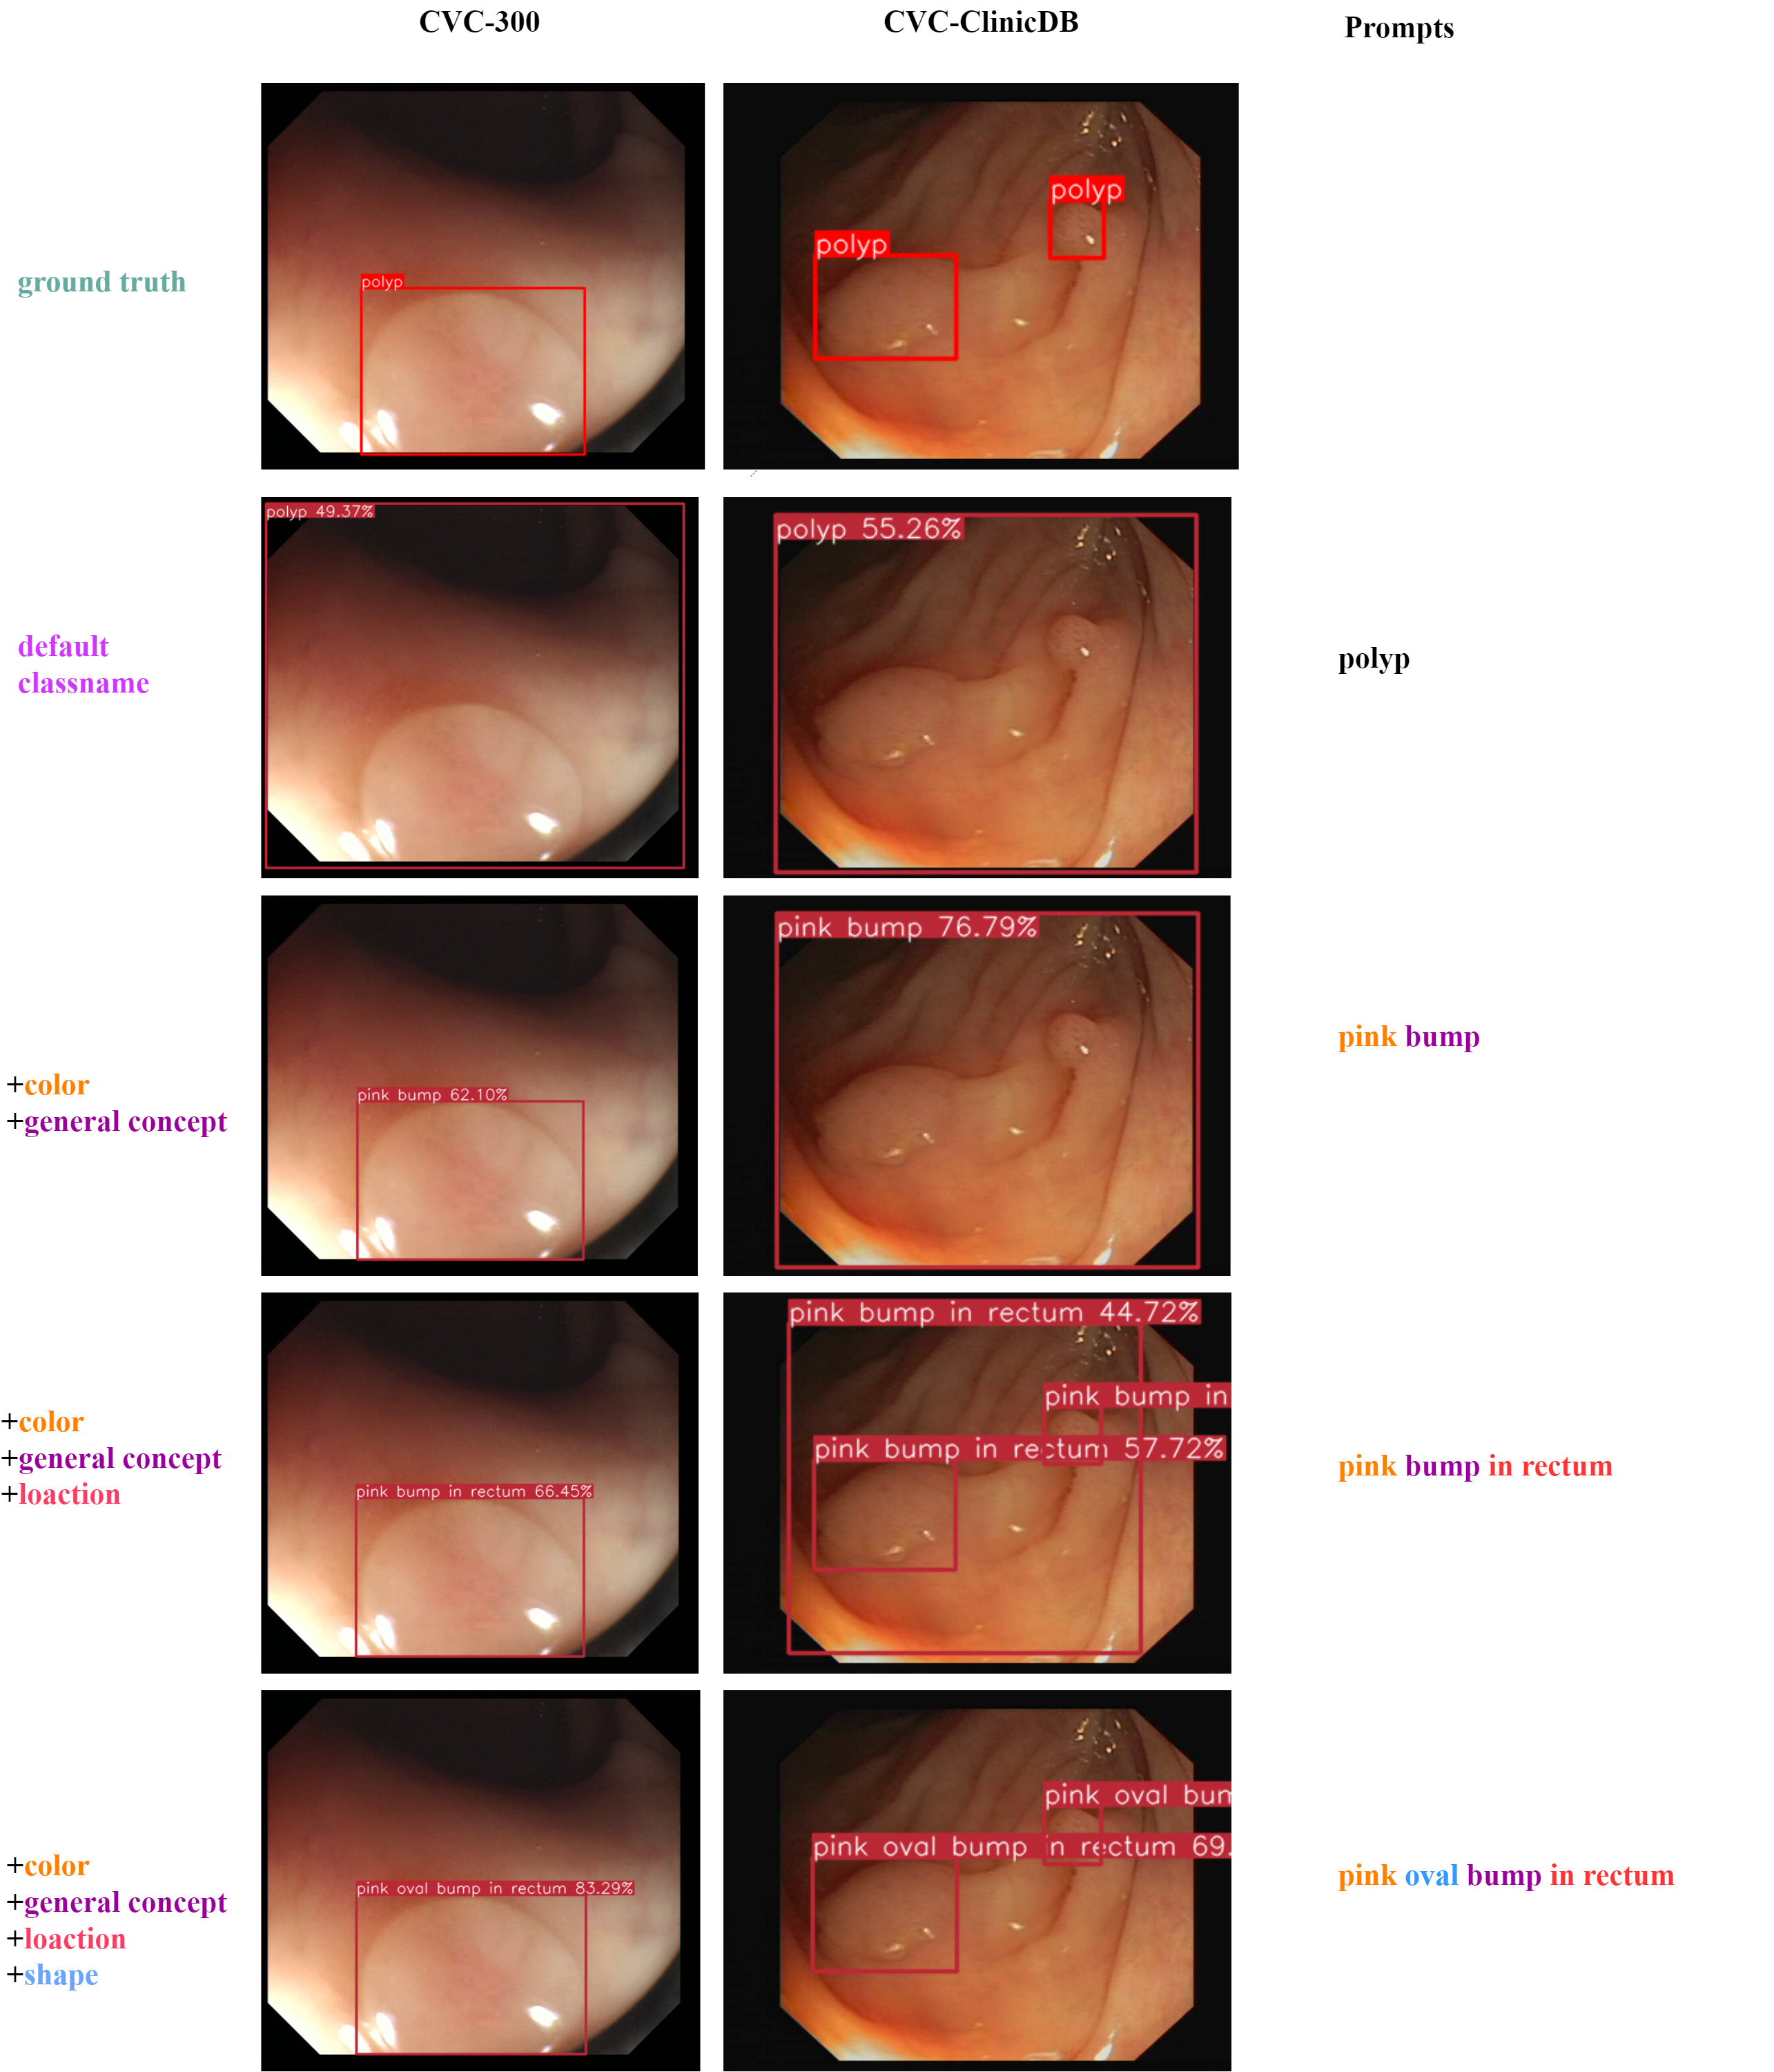

The effectiveness of attribution injection and auto-prompts In section 3.2, we discussed that adding attributes could make the models perform better in zero-shot tasks. Here, we demonstrate in Figure 3 (left) an overall pattern of the effect of attribute injection on performance under the zero-shot setting. As shown in the figure, the overall performance increases as more attributes are integrated into the prompts. This is also illustrated in Table 4 on the BCCD dataset, where various attributes and their combinations are shown to improve the results. As this process is rather tedious and time consuming, we need qualified automatic approaches to accelerate the generation process to scale up without sacrificing too much performance. Fortunately, the models with our proposed auto-prompts, especially with the hybrid and MLM-driven approaches, show comparable results to those with manually created prompts and surpass those with default prompts by a landslide. For example, the MLM-driven approach achieves an AP of 24.8% for zero-shot on the DFUC2022 dataset, while the GLIP-T baseline with default prompts only gives 0.1% for the zero-shot performance (Table 2). Figure 4 shows an example of the auto-prompt generation with the hybrid approach.

Appendix G Visualization

In this section, we provide some visualized examples to illustrate how attribute injection in prompts could affect the object detection for novel objects. In Figure 8, as we include more expressive attributes to the prompts, the predicted bbox can locate the target objects more accurately and confidently.